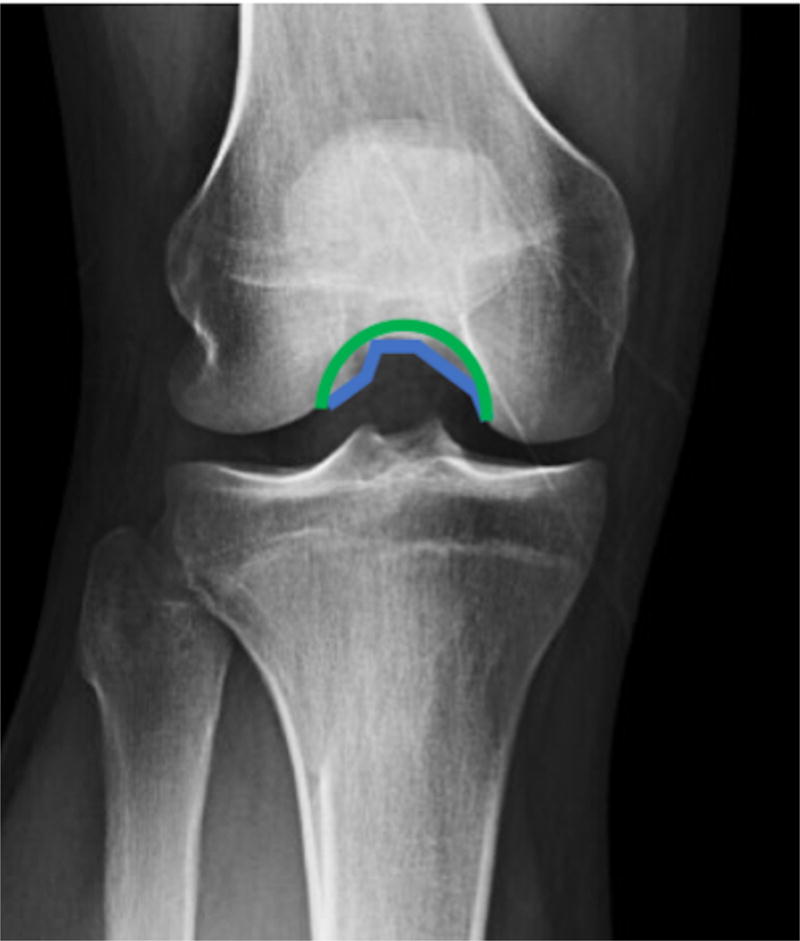

Variations in femoral morphology have also been reported to influenceknee kinematics. Differences in intercondylar notch morphology are the most commonly reported bone feature on the femoral side to be associated with ACL injury. Eggerding et al., followed 257 patients prospectively after ACL injury to determine if morphological features identified on radiographs could predict IKDC knee stability scores.27 Statistical shape modeling, which is an unbiased method for determining unique shape features common within a group of patients, was used to explore bony geometry on lateral and 45-degree, bent-knee PA radiographs. A pyramidal-shaped intercondylar notch was associated with higher IKDC scores 2 years after injury as compared to patients with dome-shaped intercondylar notches (Figure 3). This pyramidal shape of the intercondylar notch was theorized to lead to a more intrinsically stable joint that relies less on ligamentous function. As demonstrated in this study, certain bone features may help in predicting which patients will tolerate an ACL-deficiency state while others may continue to have instability following anatomic ACL reconstruction.

Figure 3.

The intercondylar notch shape has been implicated as a risk factor for ACL injury. A pyramidal shape notch shape, present in this patient and outlined in blue, may lead to greater bony congruity of the knee and was found to be associated with better knee stability scores at two years after non-operatively treated ACL injuries as compared to a dome-shaped notch, outlined in green.